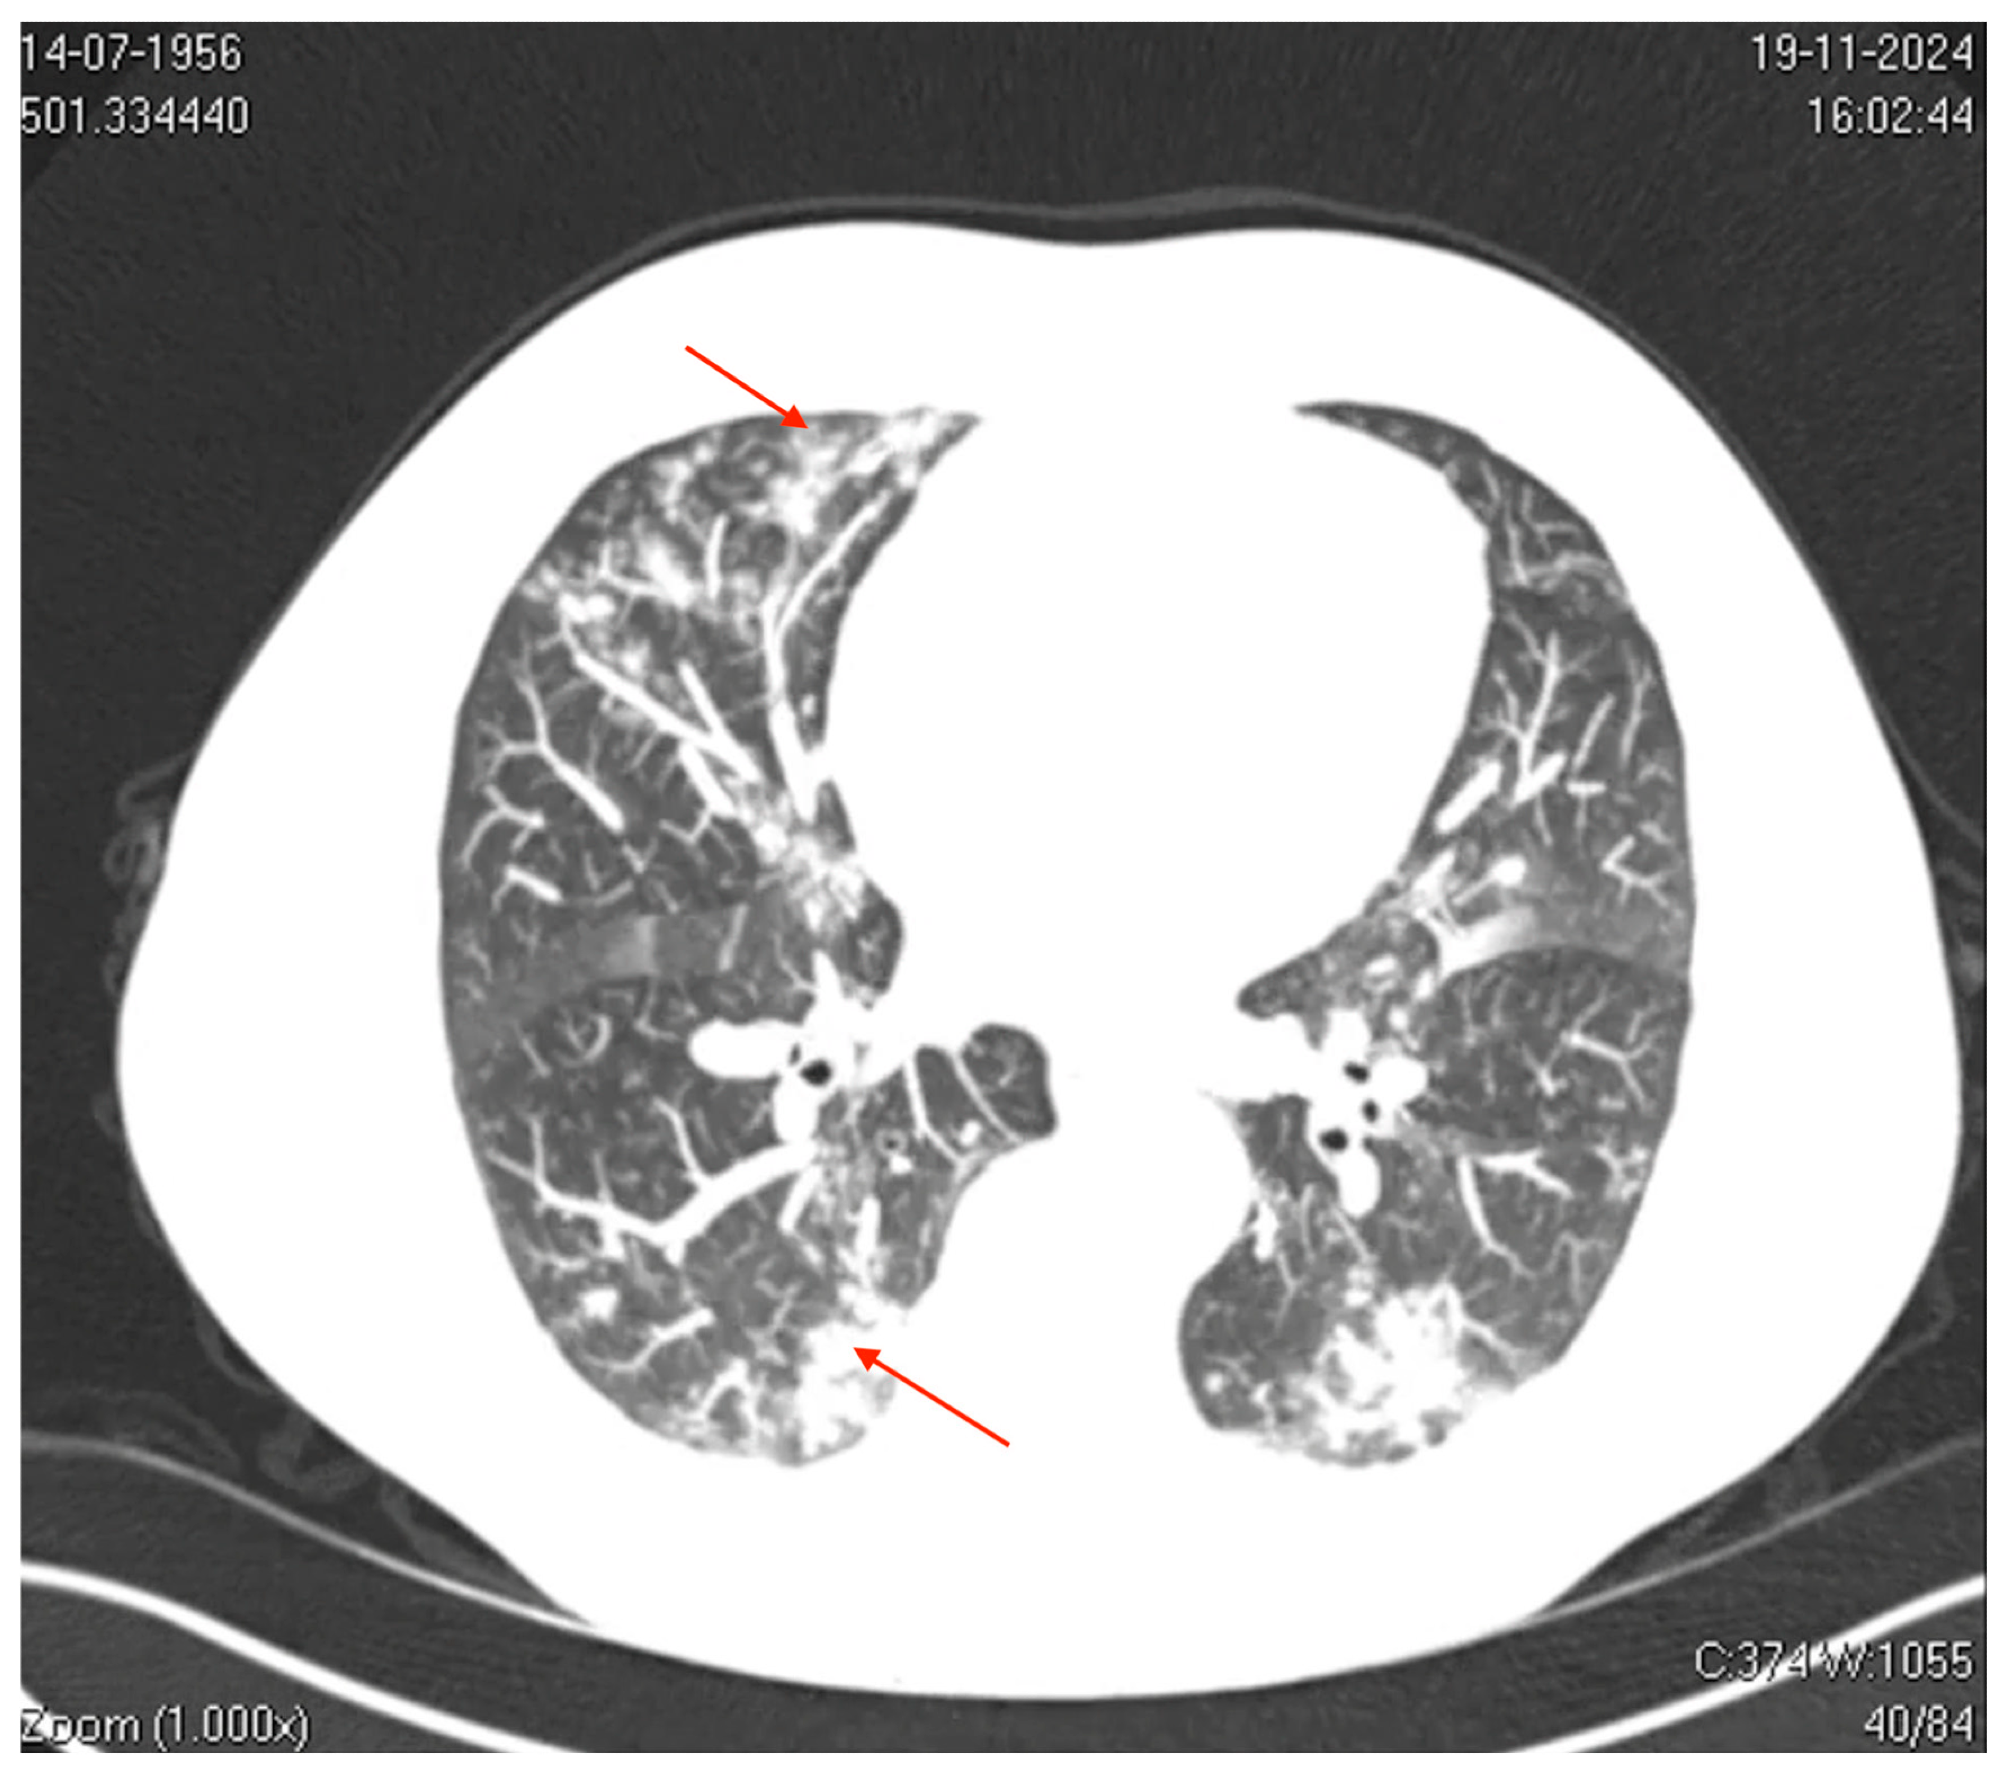

Axial computed tomography (CT) image of the thorax. The image shows bilateral ground-glass opacities with a reticular pattern interspersed with focal areas of consolidation and peripheral bronchiolar filling. The red arrows highlight specific areas of consolidation surrounded by ground-glass opacities, which are more prominent in the peripheral and lower lung regions. These findings suggest a diffuse inflammatory or infectious process involving the pulmonary interstitial and peripheral airways (acinus and bronchioles), which is consistent with viral pneumonia.

Nevertheless, the patient’s condition was exacerbated, with intense coughing, bronchospasm, myalgia, fatigue, and headache, prompting admission to the emergency department on D7. Laboratory findings revealed elevated inflammatory markers, including C-reactive protein (7.6 mg/dL) and D-dimer (870 ng/mL), thrombocytopenia, mild increase in transaminase, and normal procalcitonin and leucocyte levels, suggesting viral etiology. Imaging studies indicated significant pulmonary involvement.

Thoracic computed tomography (CT) showed mild bilateral pleural effusions, ground-glass opacities interspersed with areas of consolidation, and small centrilobular opacities. These findings were consistent with a viral pneumonia pattern and predominantly affected the left lower and upper lobes. Besides, CT of the paranasal sinuses revealed mucosal thickening in the frontal sinus.

The present study underscores that hMPV can cause significant pneumonia in immunocompetent adults with no comorbidities. This highlights the growing recognition of hMPV as a frequent cause of CAP in different age groups, especially with the decline of bacterial infections. Radiological findings, such as ground-glass opacities and bilateral consolidations, are characteristic of viral pneumonia, further supporting the diagnosis. Notably, despite molecular testing revealing hMPV as the sole pathogen, antibiotic therapy was started, reflecting persistent diagnostic uncertainty in differentiating bacterial and viral infections.